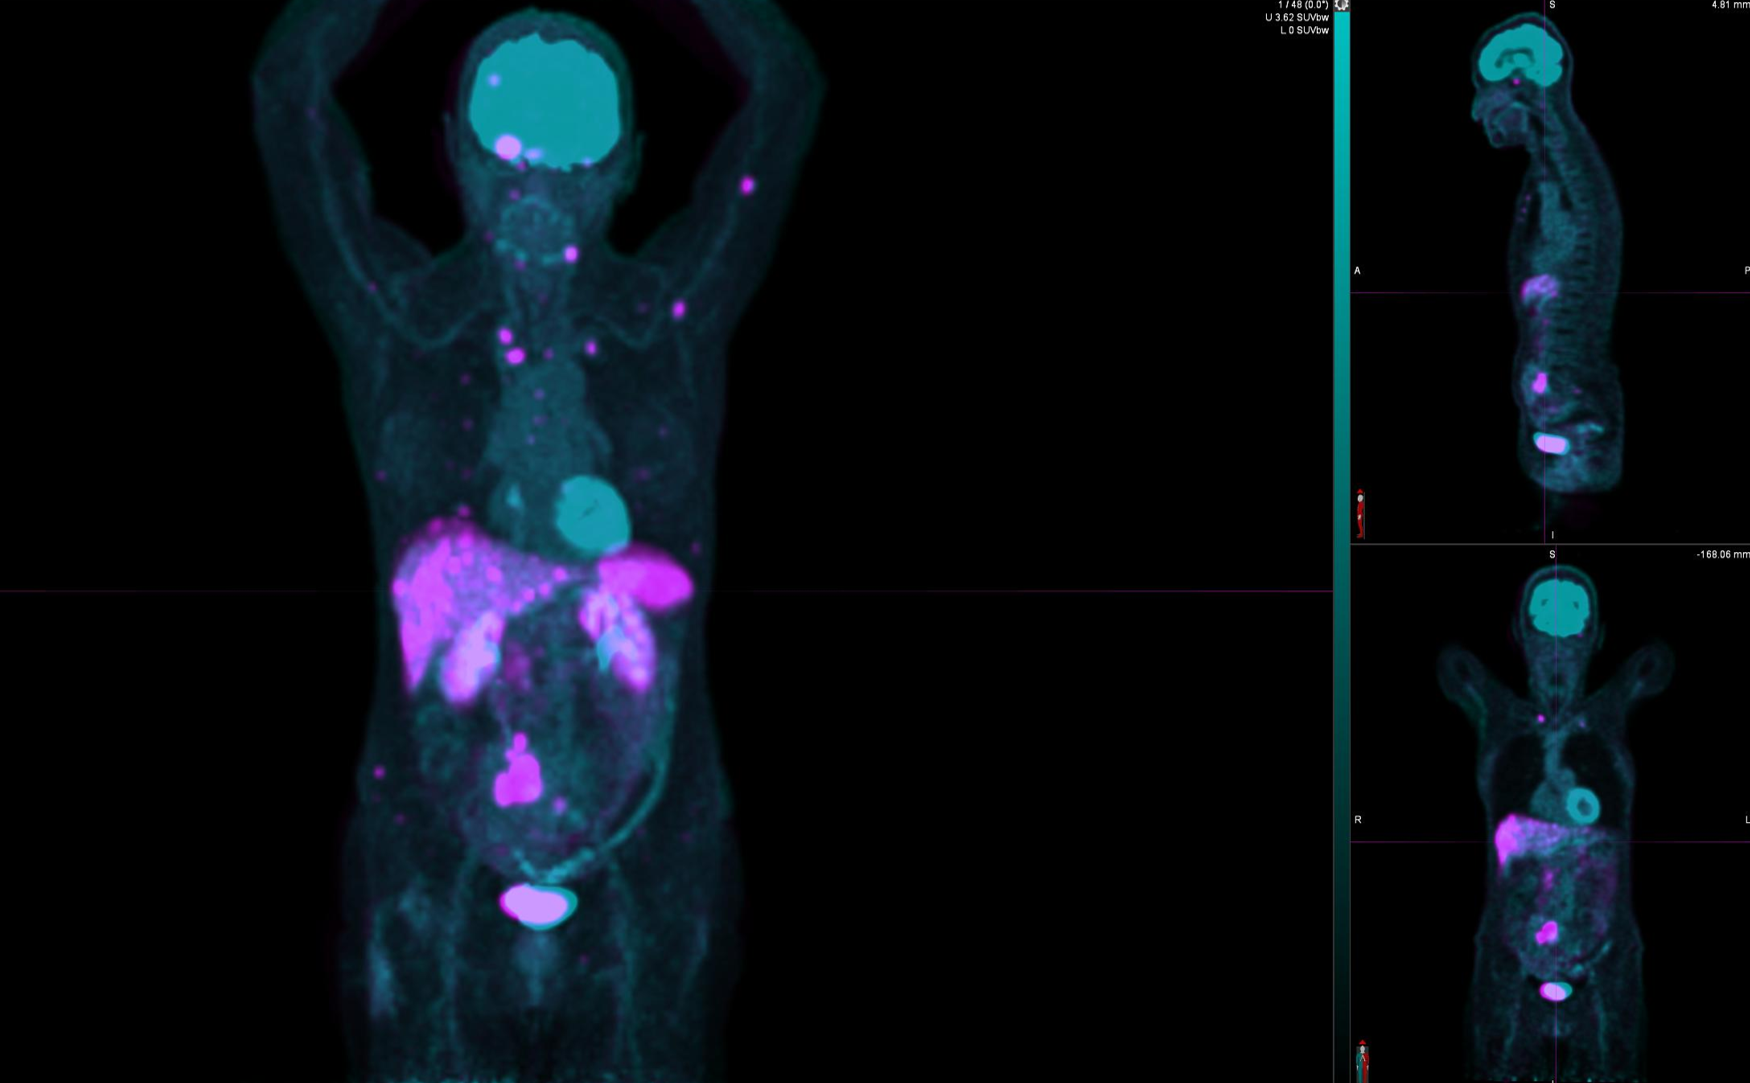

Η θεραπεία με Lu-177 DOTATATE (PRRT – Peptide Receptor Radionuclide Therapy) αποτελεί μια από τις πλέον εξελιγμένες μορφές στοχευμένης ραδιονουκλιδικής θεραπείας για νευροενδοκρινείς όγκους του γαστρεντερικού και του παγκρέατος, αξιοποιώντας την υπερέκφραση των υποδοχέων σωματοστατίνης στους νεοπλασματικούς ιστούς. Η διαδικασία περιλαμβάνει τον ακριβή προσδιορισμό της έκτασης της νόσου μέσω Ga68 DOTATATE PET/CT, την επιβεβαίωση υψηλής έκφρασης υποδοχέων SSTR και στη συνέχεια τη χορήγηση του Λουτέσιο-177 DOTATATE, το οποίο δεσμεύεται εκλεκτικά στους ανωτέρω υποδοχείς. Η ενέργεια του β-εκπομπού Λουτέσιου επιτρέπει στοχευμένη κυτταροτοξική δράση μέσα στον όγκο, με ελάχιστη διασπορά σε υγιείς ιστούς. Η σύγχρονη πρακτική ενσωματώνει ειδικά λογισμικά δοσιμετρίας, που υπολογίζουν την απορροφούμενη δόση σε κρίσιμα όργανα (ήπαρ, νεφροί, μυελός) και την πραγματική δόση στον όγκο, επιτρέποντας εξατομικευμένο σχεδιασμό και βελτιστοποιημένη θεραπευτική στρατηγική. Μετά από κάθε κύκλο θεραπείας πραγματοποιείται απεικονιστικός έλεγχος, αξιολόγηση τοξικοτήτων και συνολική εκτίμηση ανταπόκρισης, καθοδηγώντας τις επόμενες φάσεις της θεραπείας. Το Lu-177 DOTATATE έχει αποδειχθεί εξαιρετικά αποτελεσματικό στη σταθεροποίηση και συχνά στη συρρίκνωση της νόσου, παρατείνοντας την επιβίωση και βελτιώνοντας σημαντικά την ποιότητα ζωής των ασθενών.

Το Lu-177 PSMA αποτελεί μια στοχευμένη ραδιονουκλιδική θεραπεία για ασθενείς με ορμονοάντοχο μεταστατικό καρκίνο του προστάτη (mCRPC), αξιοποιώντας τη υπερέκφραση του PSMA (Prostate-Specific Membrane Antigen) στα καρκινικά κύτταρα. Προηγείται PSMA PET/CT για ακριβή χαρτογράφηση της νόσου και επιβεβαίωση επαρκούς πρόσληψης του ραδιοφάρμακου. Το Lu-177 PSMA συνδέεται στους PSMA-υποδοχείς, επιτρέποντας στοχευμένη ακτινική δράση υψηλής κυτταροτοξικότητας σε μεταστατικές εστίες οστών και μαλακών μορίων. Η χρήση εξειδικευμένων δοσιμετρικών εργαλείων επιτρέπει την ποσοτική αποτίμηση της δόσης σε κρίσιμα όργανα (π.χ. σιελογόνοι αδένες, νεφροί, μυελός) και στον όγκο, συμβάλλοντας σε εξατομικευμένη θεραπευτική προσέγγιση. Μετά από κάθε κύκλο πραγματοποιείται PSMA PET/CT ή FDG PET/CT (όπου ενδείκνυται), καθώς και στενός αιματολογικός έλεγχος για αξιολόγηση της ανταπόκρισης και των πιθανών τοξικοτήτων. Η θεραπεία έχει αποδειχθεί ιδιαίτερα αποτελεσματική στη μείωση του καρκινικού φορτίου, στη βελτίωση του πόνου, στη μείωση των επιπέδων PSA και στη σημαντική παράταση του προσδόκιμου επιβίωσης σε ασθενείς με εκτεταμένη και ανθεκτική νόσο.